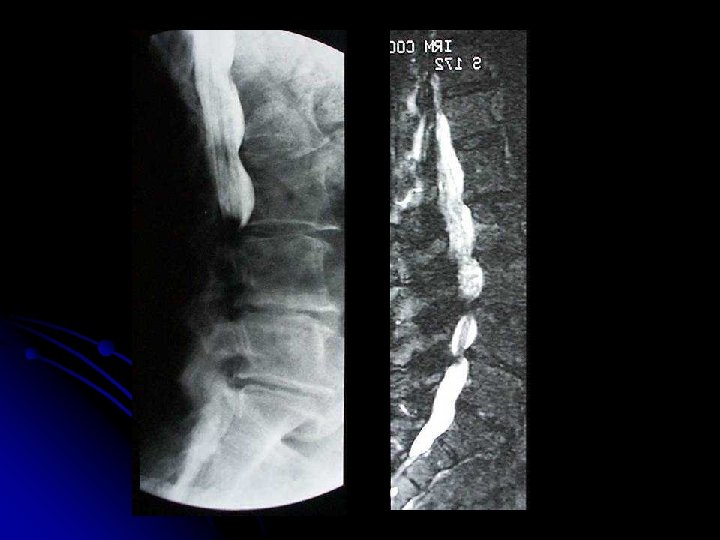

Traumatisme l RX standards l Clichés dynamiques (rachis cervical): recherche d'une instabilité postérieure l l TDM avec reconstructions multiplanaires: l bilan d'une fracture instable l Fracture du mur postérieur l luxation d'une articulation postérieure IRM: l lésion médullaire l fracture pathologique l hernie discale

Lésions dégénératives et inflammatoires l l RX standards: l troubles de la statique, l malformations, l Arthrose, l ostéochondrose (Scheuermann) IRM: l syndrome douloureux radiculaire déficitaire (hernie discale, kyste synovial intracanalaire, arthrose postérieure, sténose des trous de conjugaison), l l syndrome douloureux résistant au traitement, l claudication neurogène (canal étroit) CT: l Hernie discale l Bilan préop d’une sténose canalaire « myéloscanner »